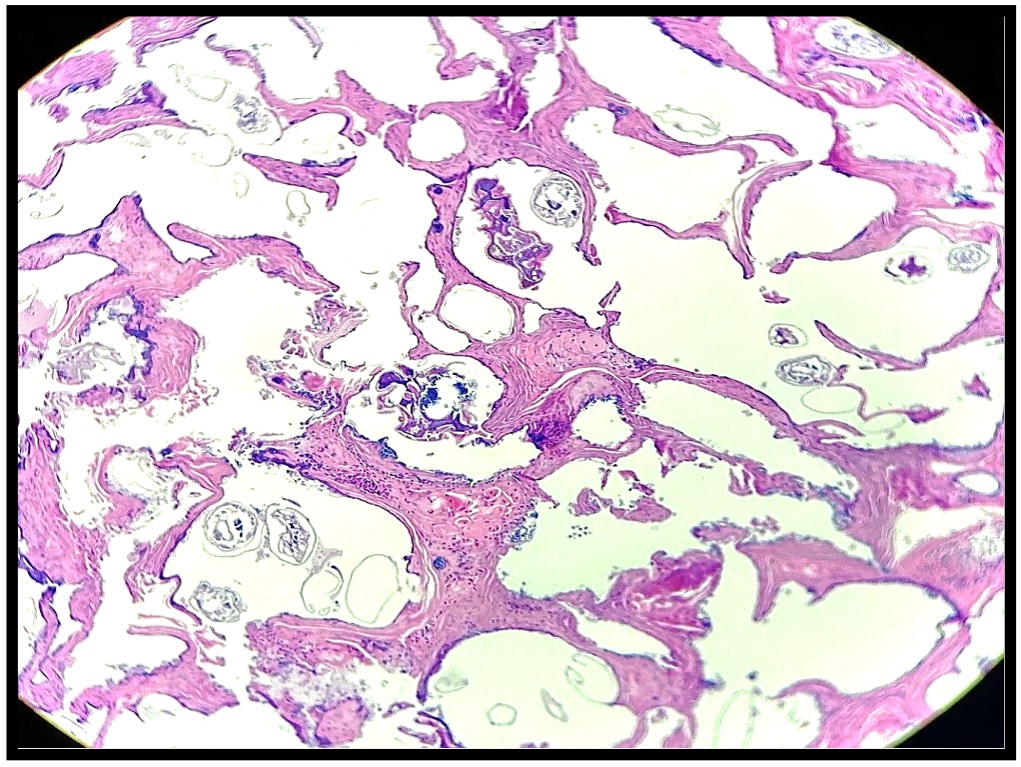

3. Cual es su diagnóstico histopatológico

B. Sarna costrosa

También conocida como Sarna Noruega, es una acarosis altamente contagiosa. Se presenta como un cuadro de queratoderma polimórfico, con lesiones maculopapulovesiculares, eccematosas o pustulares, de distribución acral y con queratosis subungueal.

La sarna costrosa, también llamada sarna noruega, tiende a darle a la piel una apariencia seca y escamosa, y a afectar zonas extensas del cuerpo.

La sarna noruega es una zooparasitosis poco frecuente y altamente contagiosa, consecuencia de la infestación por Sarcoptes Scabiei, variedad hominis o arador de la sarna; que fue descrita por primera vez en Noruega por Danielsenn y Boeck, en pacientes con lepra lepromatosa, en 1848.